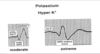

What is the effect of hyperkalemia on HR?

Bradycardia